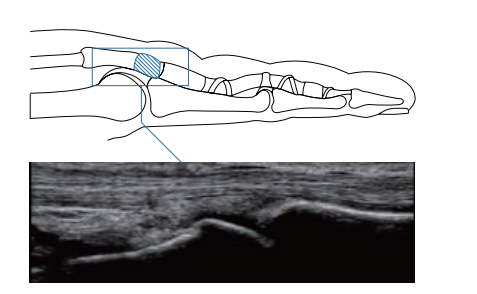

The Simple Needle Visualization (SNV) technology enhances the needle visualization on the ultrasound image. SNV is straightforward and effective and supports ultrasound-guided procedures, performed with both in-plane and out-of-plane approaches. For in-plane interventions Sonimage HS1 detects automatically the needle, optimizing its visualization.